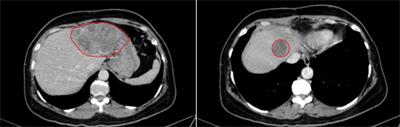

Ca lâm sàng: Điều trị ung thư biểu mô tế bào gan bằng thuốc điều trị đích Sorafenib tại Trung tâm Y học hạt nhân và Ung bướu, Bệnh viện Bạch Mai. Ngày đăng: 29/01/2026 Ung thư biểu mô tế bào gan (hepatocellular carcinoma –HCC) là loại ung thư thường gặp đứng thứ hai theo ghi nhận của Tổ chức Globocan Việt Nam năm 2022, ước tính mỗi năm có 24,502 trường hợp bệnh...